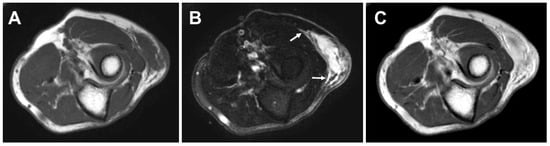

Magnetic resonance imaging (MRI) is the preferred modality to evaluate soft tissue masses in routine sarcoma clinical practice. In addition, MRI is critical for optimal surgical planning. On MRI, the lesions are typically nodular or lobular in shape and display low to intermediate signal intensity on T1-weighted images and high signal intensity on T2-weighted images (Figure 1). Heterogeneity is often noted with all MR pulse sequences, particularly in high-grade MFS. An infiltrative growth pattern, referred to as a tail sign, can be seen on fluid-sensitive sequences [,,,]. The tail sign is not only valuable for suggesting the diagnosis of MFS, but its recognition is also essential in preoperative planning. Moreover, the presence of a tail sign has been recognized as a prognostic predictor for MFS [,,,,,]. Hemorrhage and necrosis may be seen within higher-grade lesions. In our experience, subcutaneous lesions may reveal perilesional edema likely owing to the lack of a pseudocapsule. Recently, Mühlhofer et al. reported that perilesional diffuse edema was significantly correlated with a poor OS []. Contrast-enhanced MRI demonstrates nodular and peripheral enhancement of the solid components. Diffuse enhancement may also be present in higher-grade lesions []. We believe that the use of contrast is essential to distinguish the tail sign from edema.

Figure 1.

Axial magnetic resonance imaging of high-grade myxofibrosarcoma in the left elbow of a 71-year-old man. The lesion shows intermediate signal intensity on T1-weighted sequence (A) and very high signal intensity on T2-weighted spectral presaturation with inversion recovery (STIR) sequence (B). A tail sign (arrows) can be seen on STIR sequence. Contrast-enhanced T1-weighted sequence (C) demonstrates diffuse enhancement of the lesion.